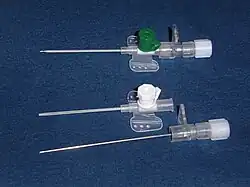

Zum Legen von peripheren Venenkathetern werden spezielle Kanülen verwendet (oft nach dem größten Hersteller als „Braunüle“ bezeichnet), die zusätzlich von einem Kunststoffrohr umgeben sind, das 2 bis 3 mm kürzer ist, als die Metallkanüle. Nach dem „Anstechen“ (Punktieren) der Vene wird die Metallkanüle herausgezogen, das Kunststoffröhrchen, welches die hintere Venenwand nicht durchsticht und gering biegsam ist, wird auf der Haut fixiert und kann ohne Wechsel einige Tage verbleiben.

Eine Sonderform der Injektionsnadeln sind die beidseitig scharf angeschliffenen Nadeln für Karpulenspritzen. Weiterhin gibt es dünne Nadeln für die Feinnadelbiopsie. Für die Lumbalpunktion gibt es ebenfalls spezielle, besonders lange und dünne Kanülen mit Mandrin, welcher während der Punktion das Verstopfen verhindern soll und die eigentliche Kanüle mechanisch stabilisiert.

Nadel für Venenkatheter

Nadel für Venenkatheter